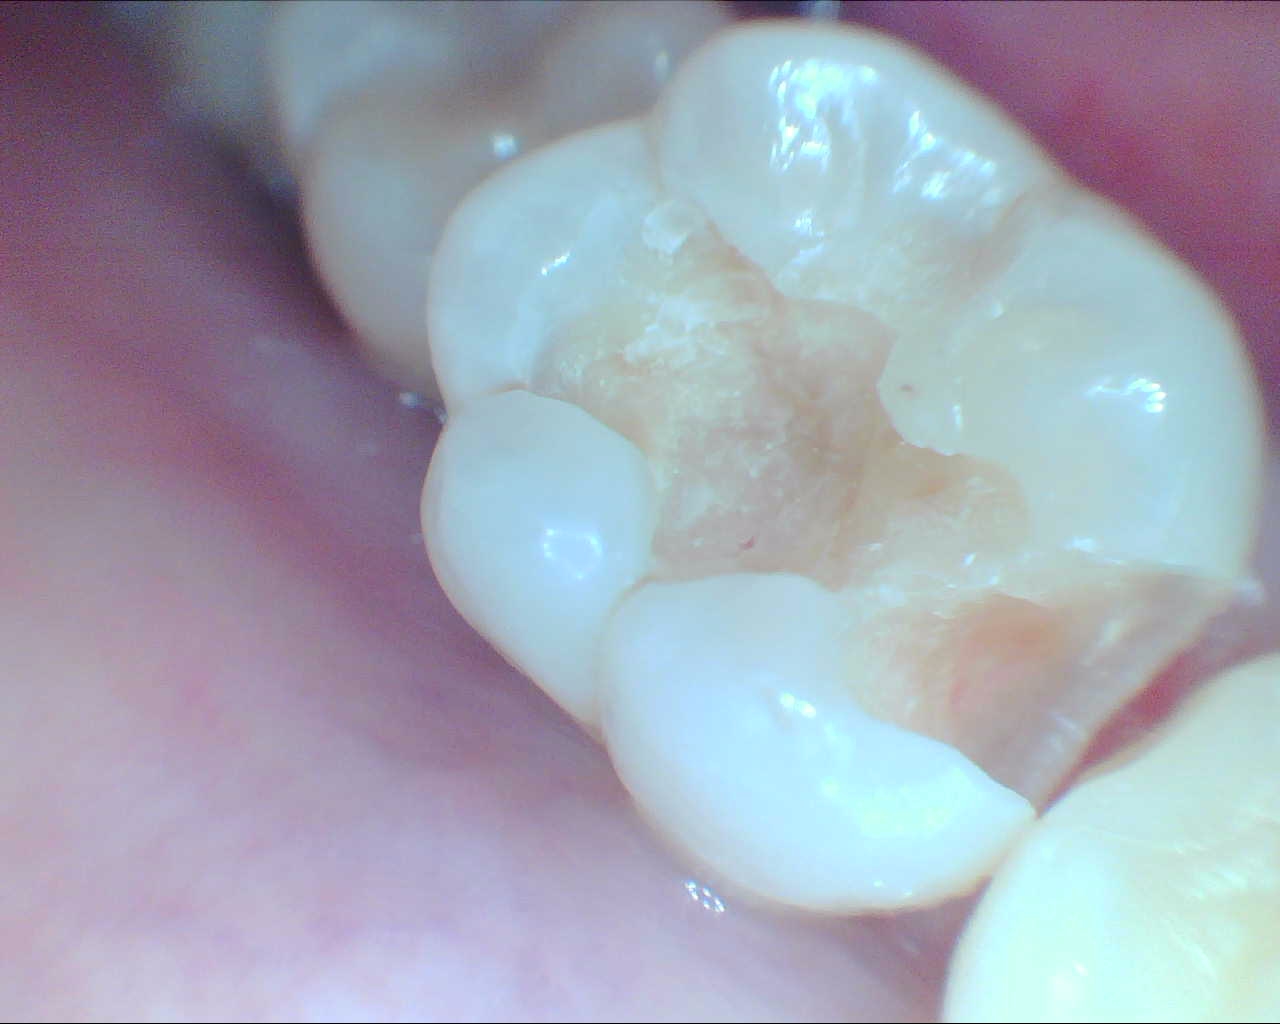

術前はこんな感じです。問題の歯は右下6番です。

歯のうえの面(咬合面)にはすでにレジン充填がしてあります。画面真ん中あたりに小さい穴があり、その周囲が茶色っぽく透けて見えるかと思います。この部分が中でむし歯になっています。